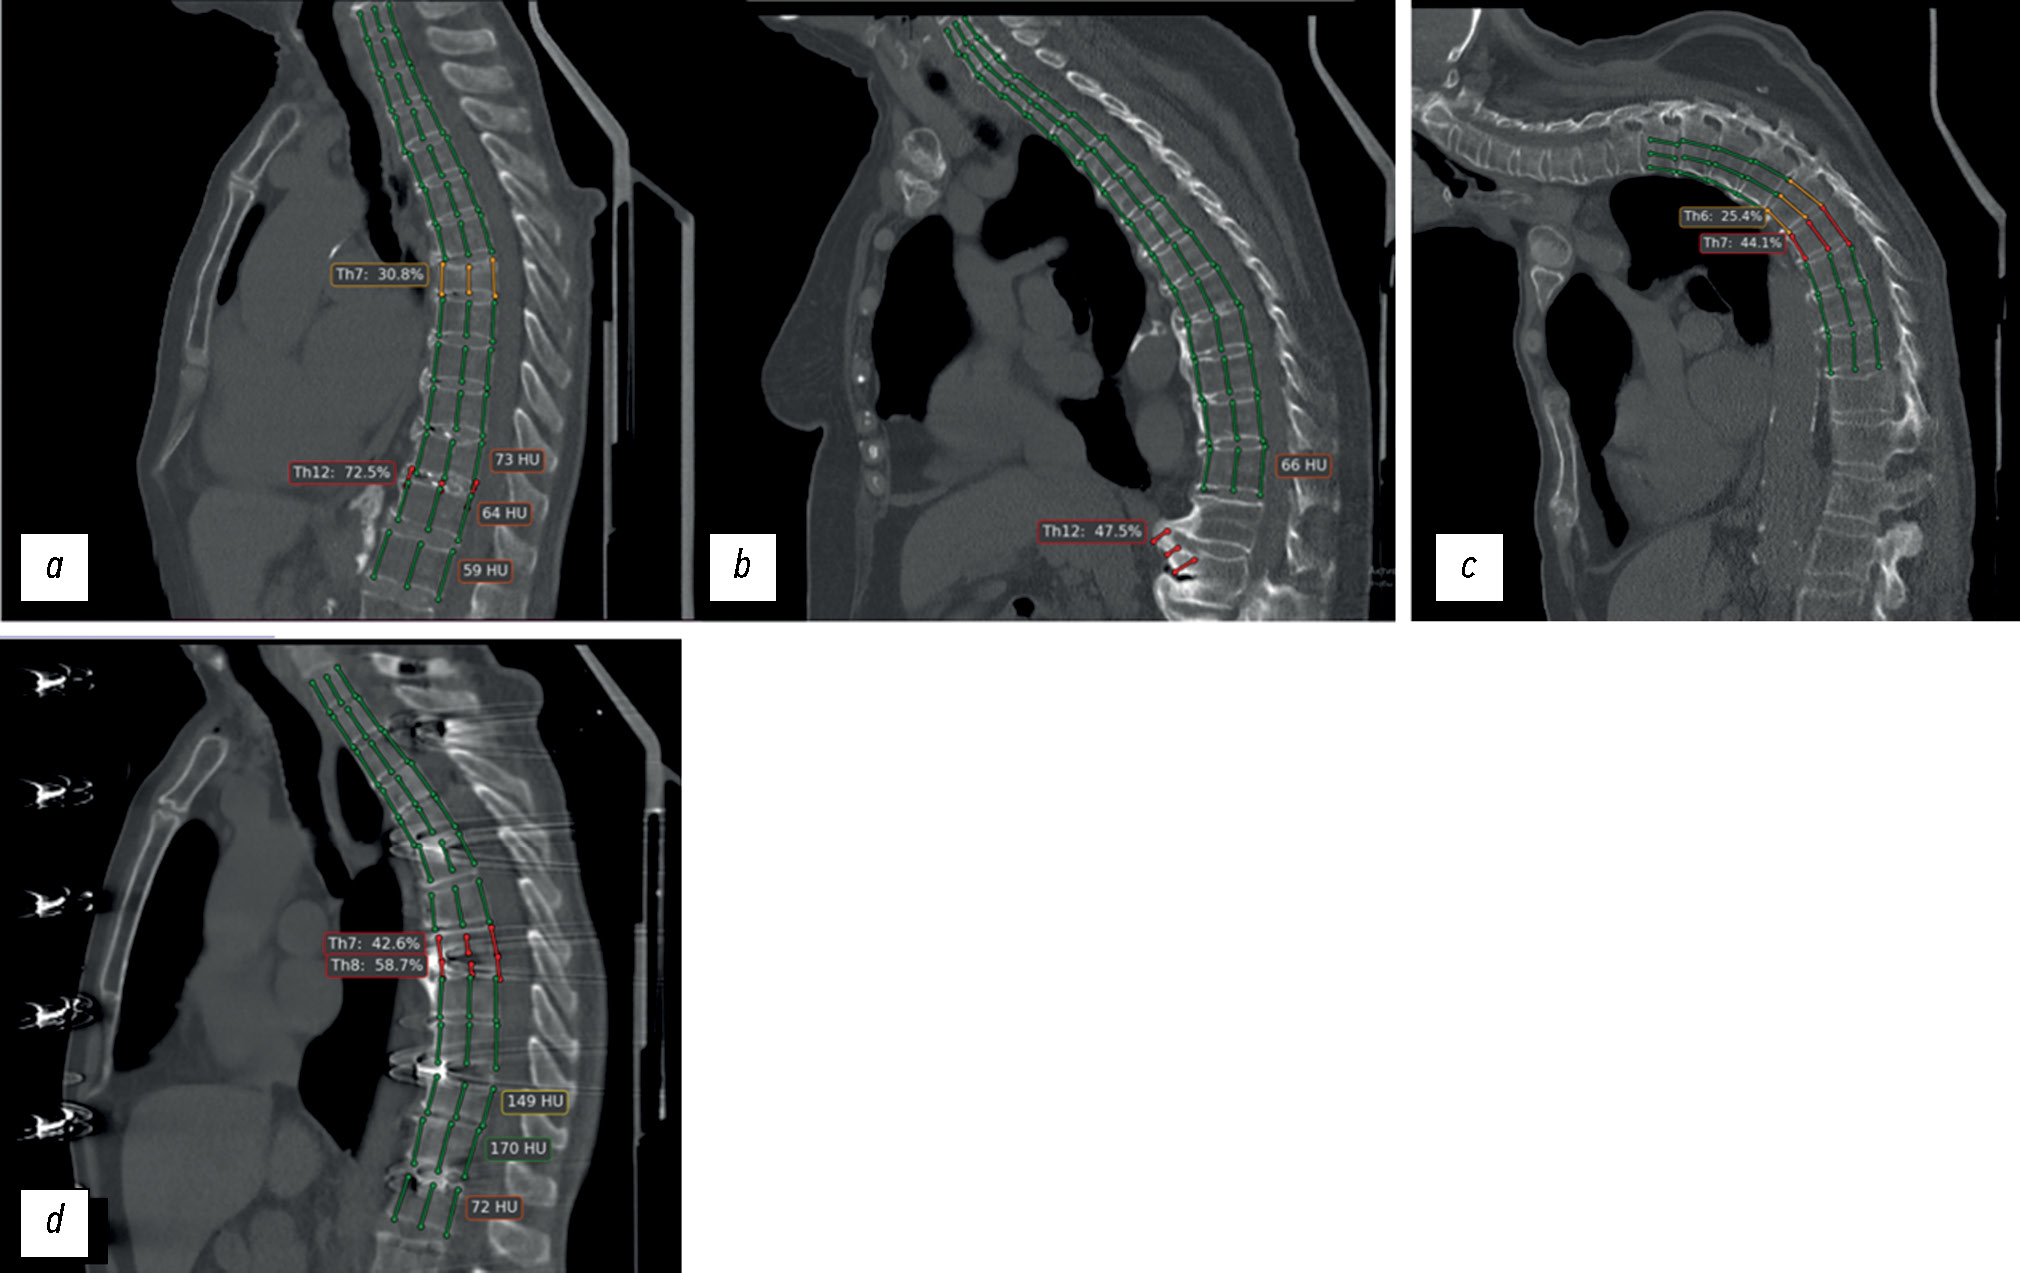

ИИ-сервис № 1, основанный на свёрточных нейронных сетях (convolutional neural networks), осуществляет морфометрическую оценку тел позвонков [20]. Результаты работы сервиса имеют вид реконструированного сагиттального среза толщиной 1 см в виде криволинейной проекции вдоль позвоночного столба. ИИ-сервис № 1 автоматически определяет вентральную, срединную и дорсальную высоту тел позвонков с последующим расчётом степени компрессионной деформации и дифференцировки по классификации Genant:

- Genant 1 — деформация до 25% (разметка отмечена зелёным);

- Genant 2 — деформация 25–40% (отмечено жёлтым);

- Genant 3 — деформация от 40% (отмечено красным) (рис. 2) [14].

Рис. 2. Пример работы сервиса Genant-IRA: дополнительная криволинейная реконструированная серия компьютерного томографического исследования с разметкой целевой патологии — компрессионного перелома тела позвонка ThXII.

ИИ-сервис № 2 осуществляет полуколичественную оценку. Данный сервис также основан на свёрточных нейронных сетях с последующим использованием рекуррентной нейронной сети для прогнозирования наличия деформации тела позвонка (рис. 3) [21]. Результат работы ИИ-сервиса № 2 представляется в виде трёх строго сагиттальных срезов (что позволяет визуализировать целевую патологию у пациентов со сколиозом), на которых отмечено тело позвонка с максимальной деформацией (см. рис. 3). При отсутствии деформации в дополнительной серии отображается надпись: «Целевая патология не обнаружена».

Рис. 3. Примеры работы сервиса HealthVCF: дополнительная серия компьютерного томографического исследования с разметкой целевой патологии — компрессионного перелома.

Рис. 6. Примеры ошибок работы сервиса Genant-IRA: a — ложноположительный результат: сервис отметил обызвествлённый межпозвонковый диск ThXI–ThXII как тело позвонка ThXII с компрессионной деформацией >40% (Genant 3); b — ложноположительный результат: сервис отметил выраженный остеофит LI как тело позвонка ThXII с компрессионной деформацией >40% (Genant 3), при этом тело позвонка ThXII не размечено; c — ложноположительный результат: у пациента с выраженным сколиозом произошло критическое нарушение работы алгоритма (так называемый слом алгоритма), нарушение построения криволинейной реконструкции, как следствие — некорректная разметка позвонков и оценка степени их компрессионной деформации; d — ложноположительный результат: ошибочно проведена разметка и выявлена компрессионная деформация >40% (Genant 3) «тел» позвонков ThVII и ThVIII вследствие выраженных ring artefacts из-за неисправности детектора компьютерного томографического сканера. Данные о дефекте сканера переданы в техническую службу Департамента здравоохранения города Москвы.

Рис. 7. Примеры ошибок работы сервиса HealthVCF: a — ложноположительный результат и некорректная оценка локализации: отсутствие компрессионной деформации >25%; b — ложноотрицательный результат (вероятнее всего — из-за выраженного кифоза у пациента): сервис не отметил компрессионную деформацию тел позвонков более 25% (ThIV, ThV, ThVI, ThVII, LII), отметки сделаны экспертом (красные рамочки); c — ложноположительный результат: отсутствует компрессионная деформация >25% тела позвонка ThIX с грыжей Шморля; d — ложноположительный результат: сервисом ошибочно выявлена компрессионная деформация >25% тела позвонка ThVIII вследствие выраженных «ring artefacts» из-за неисправности детектора компьютерного томографического сканера. Данные о дефекте сканера переданы в техническую службу Департамента здравоохранения города Москвы.